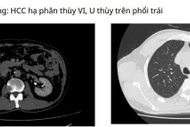

Bệnh nhân mắc 3 ung thư tiêu hóa hiếm gặp được cứu sống sau phẫu thuật phức tạp kéo dài hơn 13 tiếng, với sự phối hợp nhiều chuyên khoa.